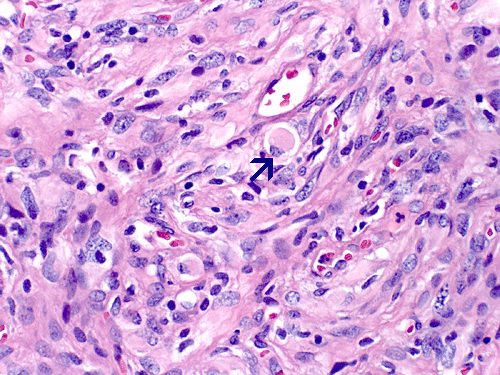

At low magnification, the lesion appears as a spindly, desmoplastic neoplasm with storiform arrangement that could be seen in some mesenchymal tumors (Panel A). On higher magnification, the overall pleomorphism is relatively mild. Mitotic figures are not readily seen. There are some round to triangular cells that are surrounded by a rim of retraction artifactual space from the surrounding desmoplastic component  (Ţ in Panel B). These cells seem like a drop of oil floating on water. The morphologic features of these cells are suggestive of ganglionic cells and/or gemistocytic astrocytes. In other areas, tumor cells containing melanin pigment (Panel C) are present. Deposition of reticulin material can be seen essentially around every single cells (Panel D). Scattered within the tumors are large ganglionic that can be well demonstrated by immunohistochemistry for synaptophysin (Panel E). Tumor cells with mature neuronal phenotype is also immunoreactive for NeuN (Panel F). Immunohistochemistry should that the amount of astrocytic cells far out numbered ganglionic cells (Panel G). Cells that express melanin are also strongly positive for HMB45 on immunohistochemistry.

Microscopically, the desmoplastic activity is so widespread that it would suggest sarcomas to the novices. Recognition of this potential pitfall is of importance during intraoperative consultations. DIA and DIG have known tendency to extend into the Vichow-Robin space. However, there is a typical, marked demarcation between the desmoplastic tumor and the cortex. Spindle cells arranged in fascicles, storiform, or wholed pattern intermixed with collagenous component are common findings and is particularly associated in areas with leptomeningeal involvement. On detailed examination, neoplastic  neuroepithelial cells with features of astrocytes, gemistocytic astrocytes, and neurons (ganglion cells) are common. It is very common that the gemistocytic astrocytes and ganglionic cells have a retraction, artifactual space at their cytoplasmic border. These large cells appear like drops of oil in water (i.e., the desmoplastic component). The collagenous component will stain blue and the neuroepithelial component will stain pink or red on Masson’s trichrome. A reticulin stain will show deposition of reticulin material around individual tumor cells. Significant nuclear pleomorphism is not a usual feature of these tumors. Mitosis is quite uncommon and the Ki-67 labeling index for cyclinc cells ranges from less than 0.5% to 5% 2. Necrosis and endothelial proliferation should not be seen. The glial component can be well demonstrated by immunohistochemistry for GFAP. The ganglionic component can be well demonstrated by immunohistochemistry for synaptophysin, neurofilament proteins, synaptophysin, NeuN, class III beta-tubulin and MAP2.